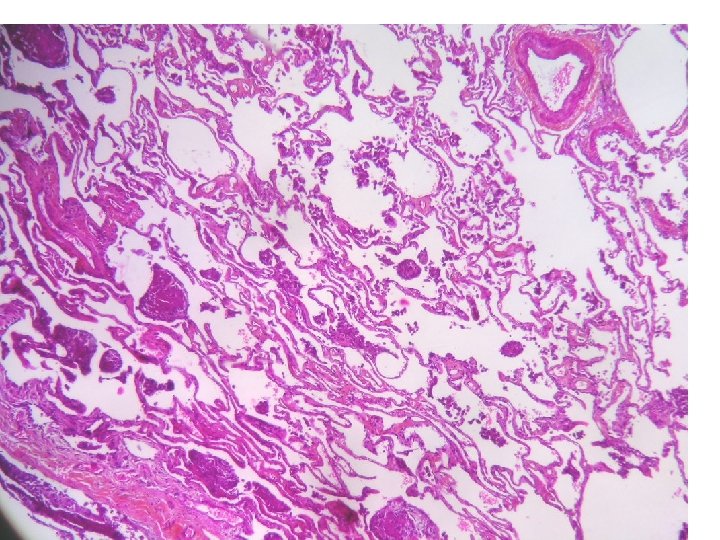

Hémosidérose localisée: poumon cardiaque

HES Perls